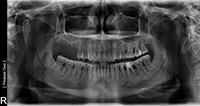

بیمار مردی 32 ساله بود که سابقه پزشکی نامطلوبی داشت. دندان آسیاب اول و دوم (دندان های شماره 2 و 3) حدودا 2 سال قبل به علت پوسیدگی گسترده خارج شد (شکل 1). ریج باقی مانده، اگر چه بسیار گسترده بود (حدود 11 میلی متر)، اما در بعد عمودی به خطر افتاده بود. اسکن های CBCT ارتفاع 5.2 میلی متری لبه ی عقبی را در ناحیه دندان شماره 2 نشان داد (شکل 2). یک ریج آسیب دیده مانند این معمولا با استفاده از روش با روش برداشت تاج سامرز درمان می شود، با استفاده از استئوتوم ها کف سینوس را به اندازه ی 4.0 تا 5.0 میلی متر بالا می کشند تا یک ایمپلنت به طول 8.0 میلی متر را قرار دهند. در محل ایمپلنت شماره 3، کف سینوس شیب رو به بالا دارد که نزدیک دیوار جلویی قرار گرفته است. ارتفاع ريج در اين ناحيه 5.9 تا 6.0 ميلي متر بود.

شکل 1: رادیوگرافی پانورامیک قبل از عمل.